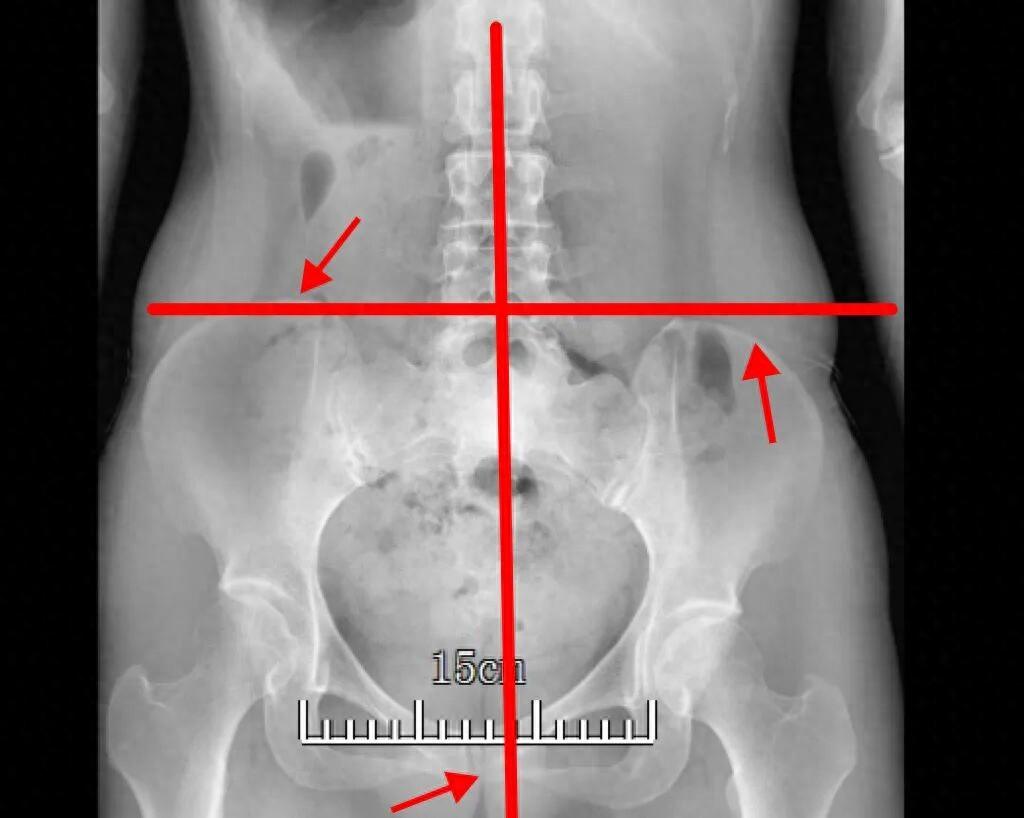

拍了片子一看,腰椎有些小毛病但並不嚴重,可讓我喫驚的是,骨盆竟然是歪的。醫生也看了、摸了我的腰部肌肉,作爲檢查的一部分。

我的骨盆居然歪了丨作者供圖

作者描述的“骨盆歪了”,即骨盆在冠狀面的不水平,稱爲骨盆上提/骨盆下沉。換言之,患者髂嵴的高度不水平,骨盆提升的一側經常被稱爲髖關節上提。

骨盆上提/下沉本質上是不對稱的拉力,導致的骨盆在冠狀面上的高度變化,大部分原因是一側肌肉的過緊,也有小部分原因是另一側肌肉的無力。一側骨盆下沉會導致另一側骨盆上提,反之亦然。

骨盆上提通常是由於軀幹同側側屈肌過度激活(緊張)所致,該肌羣跨腰骶關節與骨盆連接,最常累及的是腰方肌。大腿內側的內收肌過緊,也會導致骨盆同側上提。骨盆下沉可能是由於一側髖關節外展肌緊張,如臀中肌。

導致骨盆上提/下沉的另一個原因是一側的“肢體短縮”。這可能是由於一側的股骨或脛骨比另一側短而導致的,也可能是由於軟組織不對稱導致該側肢體的高度下降,如足弓降低而導致的功能性肢體短縮。所以骨盆上提/下沉患者,需要接受下肢長度的測量,並排查是否有功能性的肢體短縮。如果原因在於下肢,那麼需要進一步針對下肢的評估和治療。

各種原因引起骨盆上提/下沉時,因爲身體長期處於異常的姿勢,相關的肌肉會變得更加容易緊張和疼痛,這也是作者腰部疼痛的來源。

骨盆不水平的另一個影響是可能導致脊柱代償性側凸。所以,如果發現自己有骨盆不水平,可以去檢查脊柱全長片,以排查脊柱全段的姿勢問題。